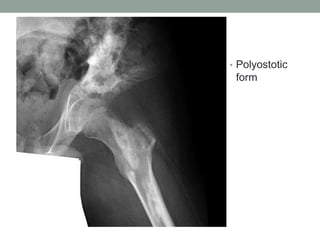

• Polyostotic

form